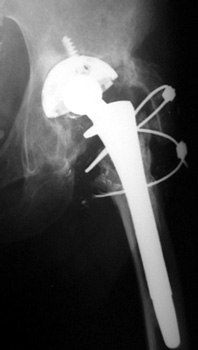

Non union of greater trochanteric osteotomy with broken and frayed cerclage cable.